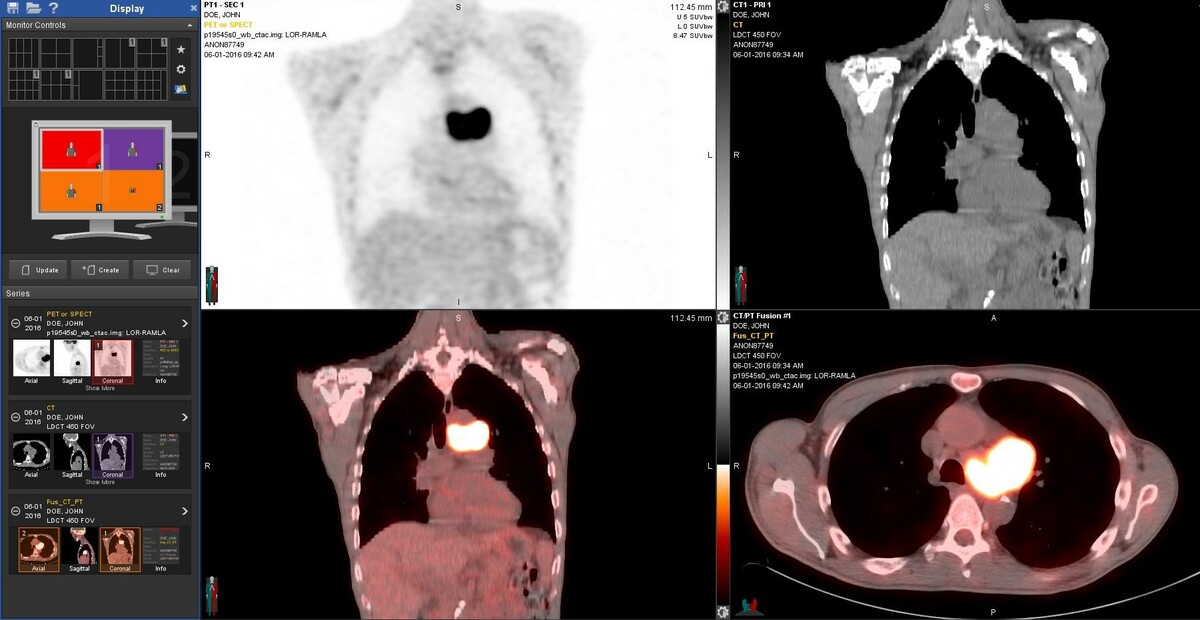

PET/CT scan showing hypermetabolic tumor within the chest.

PRI radiologists are among the most experienced in the Greater Cincinnati area in interpreting PET scans and correlating PET with other imaging modalities, such as CT and MRI.  PRI radiologists were the first to begin interpreting PET scans in the city of Cincinnati.  The PRI radiologists who interpret PET imaging have developed excellence in interpreting a high volume of PET imaging used in the initial diagnosis, staging and subsequent re-staging of many different kinds of malignancies, such as lymphoma and myeloma and cancers of the lung, breast, prostate, reproductive tract, pancreas, head and neck, and skin.  Our radiologists work closely with the referring physicians to aid the referring physician in determining the appropriate course of action or therapy for their patients.